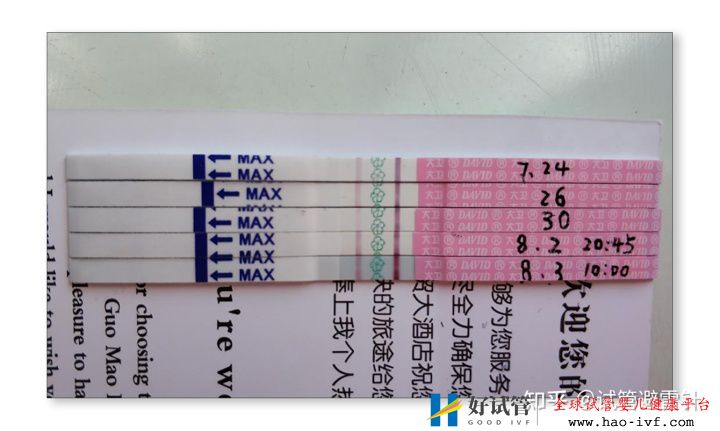

试管婴儿费用大约多少2021年:国内试管之(8)验孕

这个过程中,患者一般会在在第14天左右做B超检查,看看胚胎是否着床,尿检,抽血,并在第二天做血液取样,看看血值是否翻倍,在移植后的第30天,还有抽血看血值,看看是否有胎心和胎芽。

在移植后的第14天,用验孕测试纸可以来检验是否怀孕。试纸可以在药店买,2元一张的就可以了,不用太贵的。也建议不要过早测试,以免影响你的情绪,因为之前有些朋友在第5天就开始做检测,其实没有这样的需要,因为当时根本无法检测是否怀孕,即使检测到也是由于药物的影响,假阳性。